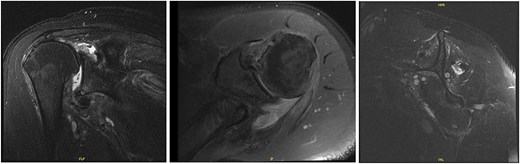

The patient continued to experience right shoulder disability, including pain, limited range of motion, and sleep disturbance. Operative intervention was delayed due to elevated liver enzymes, attributed to chronic acetaminophen use; he underwent right shoulder arthroscopy ~9 months after injury. Intraoperative findings confirmed extensive, irreparable tearing of the supraspinatus and infraspinatus, glenohumeral degenerative change, and deficient biceps tendon (Fig. 8). The joint was debrided and staged reverse total shoulder arthroplasty (rTSA) was discussed.

Intraoperative imaging of right shoulder arthroscopic debridement including findings of full-thickness supraspinatus and subscapularis tendon tears, which subsequently were not able to be repaired, as well as significant glenohumeral degenerative change.